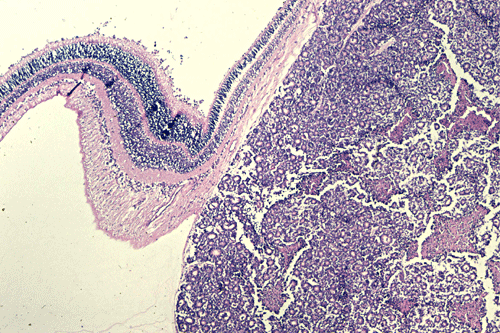

On the whole mount of the globe, there is an exophytic neoplasm that occupies about one-third the volume of the vitreous. The surface of the retina is free of tumor deposition (Panel A). The retina is detached by the mass. There are some pink, necrotic material at the core of the tumor (Panel B). On medium and high-magnification, the tumor is composed of densely packed small cells with hyperchromatic nuclei  without prominent nucleoli. A large number of the cells arrange in rossettes with a well-defined luminal border (Flexner-Wintersteiner rossettes) (Panel C and D). The tumor is confined within the globe and the optic nerve is free from invasion.

The exophytic type grows primarily from the outer retinal surface of the retina towards the choroids and is well illustrated in this case. The tumor will produce an elevation and then a detachment of the retina.  From the choroids, tumor cells invade into the orbit and conjunctiva. Extraocular extension and metastasis will follow.  Neither of these patterns carry a prognostic significance. A mixed pattern that consists of both the endophytic type and exophytic type is perhaps the most common type.